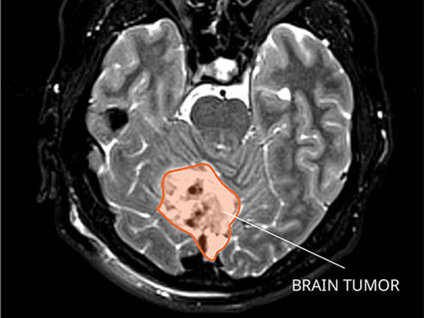

Researchers are developing liquid biopsies, tests that analyze genetic and other material in blood and other body fluids, specifically for children with solid cancers. Credit: iStock